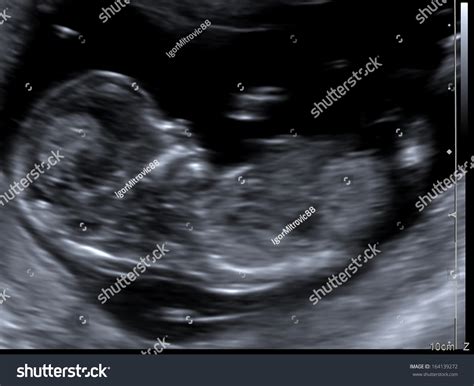

During the first and second trimesters, doctors look for specific anatomical findings. The most well-known screening takes place between 11 and 14 weeks of gestation, known as the Nuchal Translucency (NT) scan. Here are some of the markers that clinicians pay close attention to:

• down syndrome ultrasound 12 weeks

• down syndrome ultrasound 20 weeks